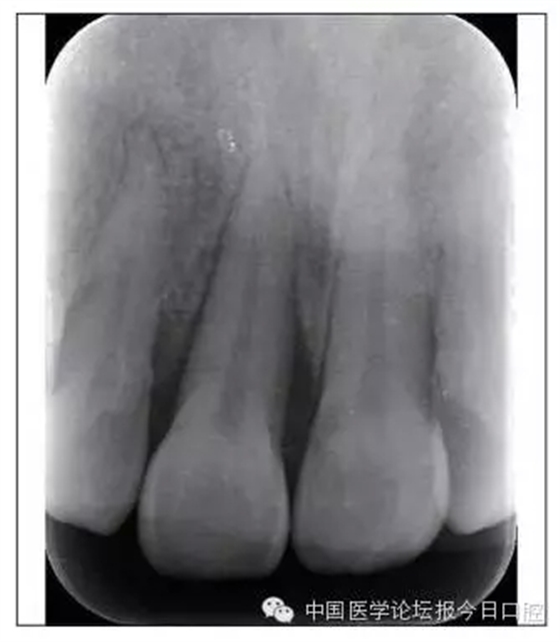

本病例為慢性牙周炎致前牙漂移、深覆(牙合)患者。本病例采用無托槽隱形矯治技術進行治療。無托槽隱形矯治器具有可摘戴、便于口腔衛(wèi)生維護和牙周治療的優(yōu)點,更適合于伴有牙周炎的錯(牙合)畸形患者的治療。 患者男,48歲,前牙有縫、前突求診。 患者面部對稱,側(cè)面觀上頜前突,下頜后縮。 口內(nèi)情況:恒牙列,24、34、44缺失,磨牙Ⅲ類關系,上牙列散隙,上前牙扇形漂移。前牙深覆(牙合)、深覆蓋??谇恍l(wèi)生較差,11與12間牙齦乳頭紅腫,多個牙探診有牙周袋形成,11松動Ⅰ度,余切牙松動(-),患者面像及口內(nèi)像如圖1、2所示。 圖1 治療前面像 圖2 治療前口內(nèi)像 全口曲面體層片(圖3)顯示,患者全牙列牙槽骨吸收;根尖片(圖4)示11近中牙槽骨角形吸收已達根尖1/3,21牙槽骨嵴頂吸收至根1/2,23牙槽骨近中骨板角形吸收至根1/2。磨牙區(qū)骨嵴頂吸收3mm。治療前頭顱側(cè)位片見圖3,治療前ODS模型見圖5。 圖4 治療前根尖片 圖5 治療前ODS模型 牙型:安氏Ⅲ類。骨型:Ⅱ類。面型:上頜前突,下頜后縮。 問題列表為:①上牙列間隙;②上切牙病理性牙移位;③前牙深覆(牙合)、深覆蓋;④24、34、44缺失;⑤慢性牙周炎。 矯治目標包括:①排齊牙列,關閉牙列間隙;②改善前牙深覆(牙合)、深覆蓋;③改善牙周狀況。 矯治設計有:①牙周基礎治療與維護。②壓低、內(nèi)收上切牙,關閉上牙列間隙。③壓低下切牙,伸長下后牙,整平Spee曲線,改善前牙覆(牙合)、覆蓋。 患者進行全口齦上潔治、齦下刮治,口腔衛(wèi)生宣教,并按牙周醫(yī)師的要求,每2~3個月行牙周檢查與治療。 牙周基礎治療結(jié)束3個月,開始隱形矯治。于14、25、35、36、45、46上粘接附件(圖6),于16、26(牙合)面粘接(牙合)墊。 圖6 ODS設計附件粘接圖示 矯治過程中注意(牙合)墊是否脫落或磨損,及時修補。 注意上前牙內(nèi)收時有無咬合干擾,及時調(diào)(牙合)。下頜前磨牙伸長到位后,磨除16、26(牙合)墊。 下頜佩戴第24步矯治器時,分別在36、37、46、47的頰、舌側(cè)粘接舌扣,矯治器上預留伸長空間,用3/16英寸、3.5盎司皮圈牽引,輔助伸長下磨牙(圖7)。 患者共戴用矯治器上頜32步,下頜26步。 矯治后,牙列間隙關閉,面型及覆(牙合)覆蓋改善。11根尖片(圖8)顯示,治療后較治療前,牙周支持組織增加,牙槽骨角形吸收區(qū)水平向縮小0.3mm,垂直向縮小0.6mm。11松動Ⅰ度,余切牙無松動。 圖8 治療后根尖片 圖9 治療后口內(nèi)像 圖10 治療后X線檢查 圖11 治療后ODS模型 正畸-牙周聯(lián)合治療對于牙周組織的影響 多學科綜合治療牙周炎患者不再是正畸治療的禁忌證。良好的牙周治療為正畸治療中的牙齒移動打下堅實基礎,而正畸治療排齊牙齒、去除(牙合)干擾,有利于牙周健康。 牙周炎患者的正畸治療必須在牙周炎癥得到控制后才能進行,否則,菌斑會隨著牙齒的移動,特別是壓低而使牙周炎癥加重。牙周炎的正確診斷、牙周炎癥控制、正畸治療中和治療后的認真維護是治療成功的關鍵。根據(jù)臨床需要,一般每2~4周做一次潔治,每3個月進行牙周評估,同時患者必須進行非常良好的日??谇恍l(wèi)生維護。 固定矯治器使得牙周檢查、潔治和日??谇恍l(wèi)生維護變得困難,隱形矯治器可自行摘戴,便于患者日常維護和牙周治療,節(jié)約時間,提高菌斑控制效果。 有臨床研究表明,對于存在(牙合)創(chuàng)傷,伴有角形吸收的患牙,經(jīng)過牙周翻瓣手術控制住牙周炎癥后,使用正畸輕力壓低患牙,可以改善牙槽骨吸收的程度,并獲得一定程度的牙周新附著。本病例切牙壓低后,原來的牙槽骨吸收有改善。 病理性牙移位 病理性牙移位(PTM)在重度牙周炎患者中的發(fā)生率為30%~50%,且常見于上前牙區(qū)。其主要由于牙周支持組織喪失尤其是骨組織的丟失,咬合因素(如后牙缺失、前牙深覆牙合、牙合創(chuàng)傷等),頰舌唇肌力量不平衡及牙周和根尖周組織炎癥所致,是牙周炎患者要求正畸治療的主要原因之一。 PTM須通過正畸、牙周聯(lián)合,有時須配合修復才能達到理想的治療效果。正畸治療通常是壓低牙齒,臨床研究表明,牙周手術配合正畸壓低可以產(chǎn)生新附著,有利于PTM牙周組織的恢復。 本病例右上中切牙牙槽骨角形吸收,在盡量保證治療前后根尖片投照角度一致的情況下,以鄰牙作為校準,在根尖片上對治療前后的骨量進行評價,治療后牙槽骨角形吸收區(qū)水平向縮小0.3 mm,垂直向縮小0.6mm。盡管根尖片并不能說明骨量改變,但從影像學上能看到骨吸收區(qū)域有所減小。 無托槽隱形矯治器矯治牙周病的優(yōu)勢 無托槽隱形矯治器具有可摘戴、便于口腔衛(wèi)生維護和牙周治療的優(yōu)點,更適合于伴有牙周炎的錯(牙合)患者的治療;同時,無托槽隱形矯治器佩戴后具有牙弓夾板和(牙合)板的作用,可有效減少側(cè)向力,有利于牙周的恢復和減輕牙齒松動;由于無托槽隱形矯治器的設計是在三維數(shù)字模型上進行的,每個矯治器移動牙齒的數(shù)量和每個牙齒的移動距離可以得到量化控制,因而可以根據(jù)患者牙槽骨水平和對矯治力的耐受情況個性化設計矯治力,并且可以根據(jù)矯治中牙齒移動情況調(diào)整后續(xù)矯治器的設計。 有關磨牙伸長 單純使用無托槽隱形矯治器同步伸長后牙比較困難。該病例先使用磨牙(牙合)墊打開咬合,通過矯治器伸長前磨牙,在前磨牙建立咬合后,磨除磨牙上的(牙合)墊,通過輔助牽引伸長磨牙,最終達到伸長后牙、整平Spee曲線的目的。 史真,主任醫(yī)師,現(xiàn)任北京黃寺整形外科醫(yī)院口腔科主任,第四軍醫(yī)大學口腔正畸學碩士,為世界正畸醫(yī)師聯(lián)盟(WFO)會員、全軍口腔醫(yī)學專業(yè)委員會委員、中華口腔正畸專業(yè)委員會委員、中華醫(yī)學美學與美容學會齒科美容學組成員、北京口腔醫(yī)學會兒童口腔專業(yè)委員會常務委員、北京口腔醫(yī)學會正畸專業(yè)委員會委員、《中華醫(yī)學美學與美容》雜志審稿專家,是我國最早開展無托槽隱形矯治技術的口腔醫(yī)師之一。